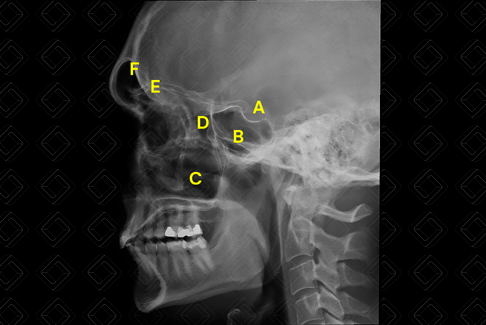

Texto alternativo para a imagem Figura 1. Radiografia dos seios da face, incidência em perfil. Créditos: Dra. Elazir Mota - Rio de Janeiro/RJ

Legenda das siglas (figura 1): A = sela túrcica; B = seio esfenoidal; C = seio maxilar; D = células etmoidais; E = teto da órbita; F = seio frontal.

• Incidência em perfil: Posicionar o lado lateral da cabeça contra a mesa / Bucky vertical, como lado de interesse mais perto do filme. Avaliar os seios esfenoides, frontais superpostos, células etmoidais e seios maxilares, sela túrcica e teto orbital. (Vide Figura 1 acima, em "Como Solicitar") ;